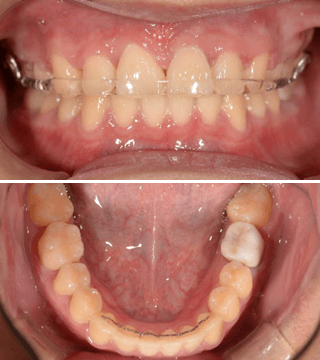

治療前

治療後

1年半の矯正治療で人生が変わることもあります。口元、笑顔の印象はそれだけインパクト大です。

動的期間1年半で終了です。

4

ブラケットを外しました。上は着脱式の保定装置、下は前歯の裏側で保定しています。